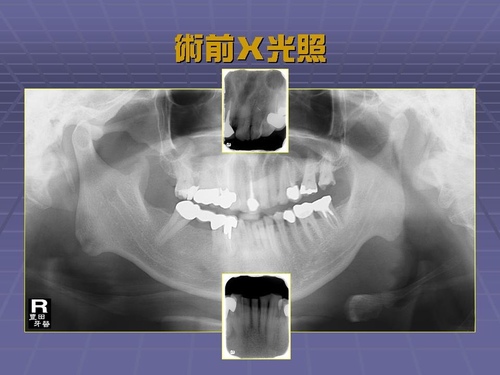

全口假牙重建

咬合設計錯誤導致的磨耗